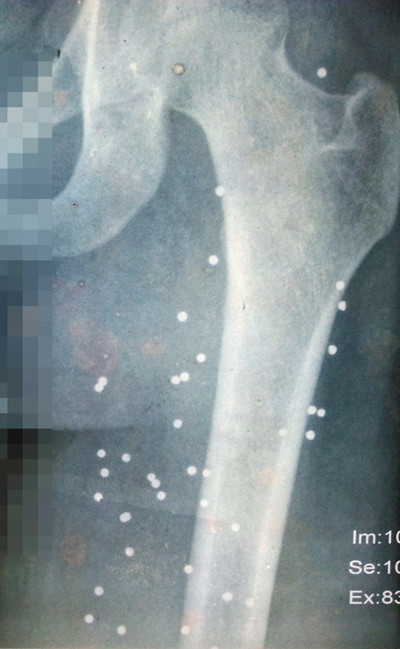

当晚在现场围观而被子弹击中的李志强现在在村里杀猪,“到现在左手还有一块骨头是软的”。而当晚连中两弹陷入昏迷的李孔华,几经转院治疗后,取出了部分霰弹,前前后后花了三万元多医疗费,“现在双腿还有170多粒霰弹无法取出(见左下图)”。因为受伤严重,李孔华一直没法外出打工或者干重活,只能在村里摆摊,勉强养家糊口。“我现在就希望这个案子能有个结果,我们无辜受伤的也能得到应有的赔偿。”